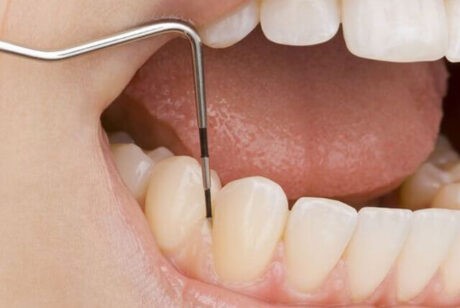

歯周病はこれまで歯槽膿漏という言葉で表されてきました。今では歯周病という言葉が一般に普及してきました。歯周病は字からもお分かりのように、歯のまわりに起こる病気です。歯のまわりにプラークや歯石がたまると歯茎が腫れ、歯と歯茎の間の隙間が大きくなります。この隙間のことを「歯周ポケット」とよびます。歯周ポケットは、歯周病原菌が繁殖するのに適した環境であり、歯周病原菌が入り込むことで、歯茎の下にある歯を支えている骨を溶かしていく病気です。

歯周病の進行度を把握するためにプラークの付着量、歯周ポケットの深さ、出血の有無、歯の動揺度などを検査します。

※歯周病の進行度合いによって少し痛みを伴うことがあります。